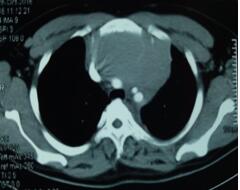

當看到病人的CT等外院各項檢查時,我頭皮發(fā)麻,心頭發(fā)怵:巨大的腫塊占據(jù)著整個縱隔,壓迫心臟,與血管關(guān)系密切,初步考慮侵襲性胸腺瘤、胸腺癌或淋巴瘤等,合并腎功能不全,無法完整切除,手術(shù)風險大,手術(shù)并不能提高病人長期生存率,換言之,小伙子等待的是生命的立即終結(jié)。